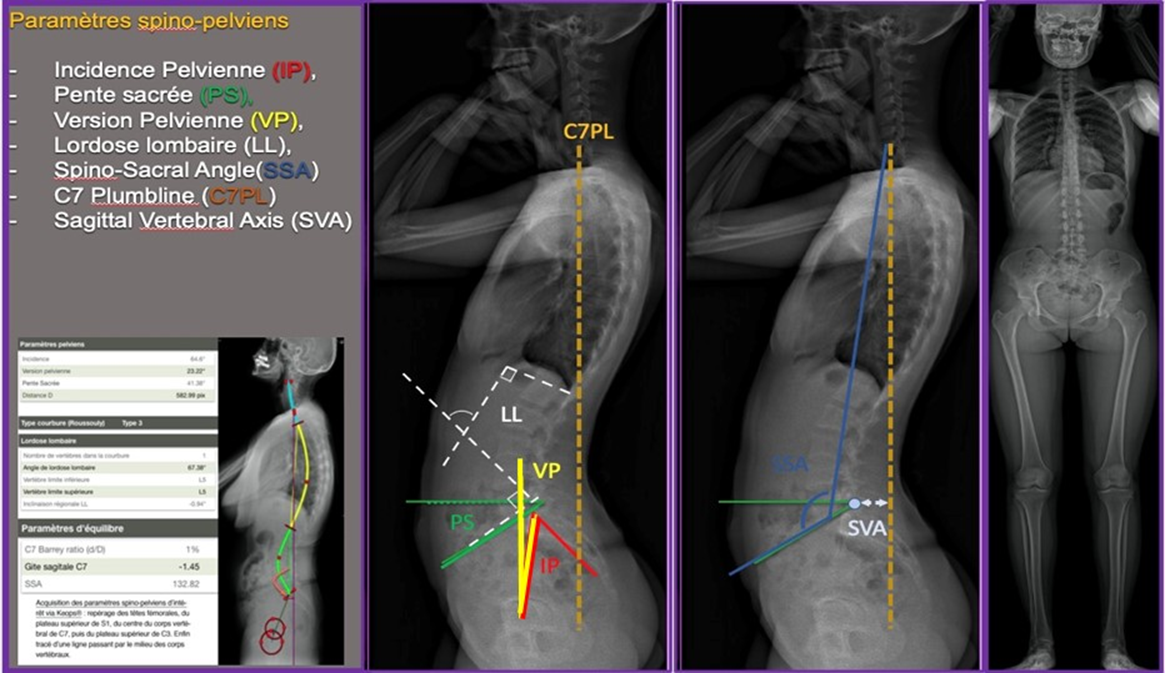

Mise au point « Hip spine syndrom » implication du complexe lombopelvien et de la hanche orientation diagnostique , Pascal Kouyoumdjian CHU Nîmes, 4 rue du professeur Robert Debré, 30029 Nîmes, France N°312 - Mars 2022 ● 32 min de lecture